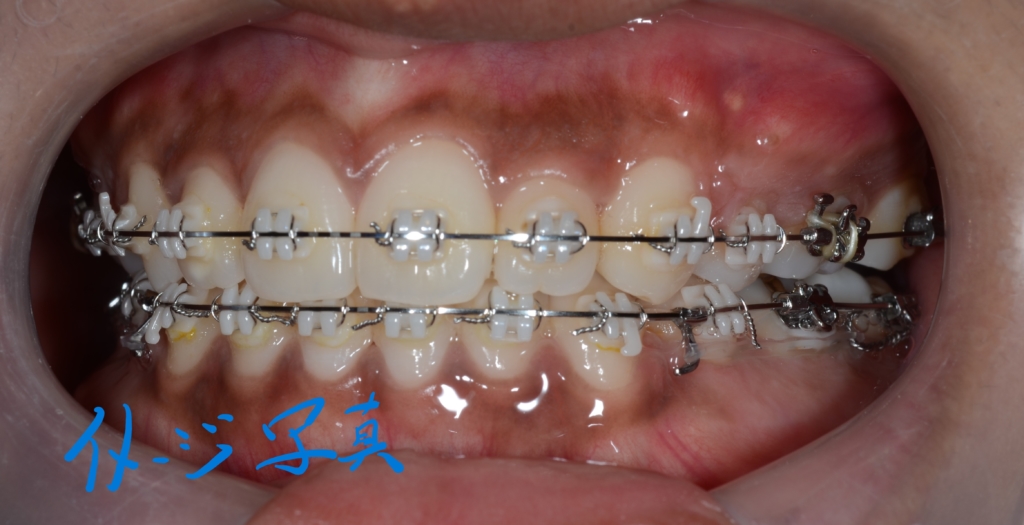

マルチブラケットシステム(フルホワイトtype)で矯正を開始。

この方の写真が見つからないので、同じことをしている他の方の写真をイメージ写真としてあげています

上下とも前歯がきれいに並んで、引っ込めるステップに入る目途がついたので、上の奥歯辺りにアンカースクリューを植立しました。

上下とも前歯を後方へ最大限に引っ込めて行きます

上顎のアンカースクリューには、PLAS & 奥歯の内側にはパラタルバーを付けて

下顎のアンカースクリューには、よじったワイヤーフックを付けて

上下の歯列(歯並び全体)を出来るだけ後方へ引っ込めて行く「矯正力」を加えて、治療を再開しました。

スイマセン・・・

この方の写真を探したのですが見つからないため、全く同じことをしている患者さんの写真を「イメージ写真」として代用しています。